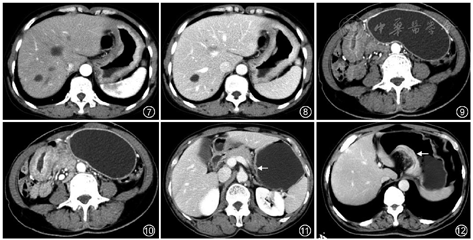

胃癌的组织学类型与患者的发病年龄、肿瘤部位、Borrmann分型、浆膜侵犯以及淋巴和远隔转移等,均是影响胃癌患者预后的主要因素[5]。CT对胃印戒细胞癌的诊断具有一定的帮助,胃印戒细胞癌多累及胃窦和胃底,累及全胃者较少,鲜有多发病灶;病灶多为肿块型和弥漫型;病灶强化模式多样,强化峰值多在静脉期,低强化区具有延迟强化的特点[6](图7,8)。Borrmann Ⅳ型胃癌在所有类型胃癌中预后最差,易发生腹膜播散转移[7],更倾向于分层强化的方式,自动脉期至平衡期,增厚的胃壁表现为由内向外的透壁性强化[8](图9,10)。对于更多病理类型的判断,目前CT存在一定的局限性,仍需更多的研究深入探讨。

1.T分期:CT检查是术前评估胃癌T分期的常规手段,但胃壁组织学上的5层结构(黏膜层、黏膜肌层、黏膜下层、固有肌层、浆膜层)在CT图像中很难完整显示,尤其是对于早期胃癌的诊断和浆膜层侵犯的评估,因此胃癌CT评估T分期的准确率还有待提高[9]。近年来,关于T分期的CT征象研究取得了一定的进展,如通过“双轨征”诊断早期胃癌,其典型表现为胃壁稍增厚,黏膜层明显强化,胃壁外层稍高强化,中间呈条带状低密度(图11);浆膜面高强化线征(图12)是区分胃癌T3和T4a期的有效征象,该征象与浆膜面侵犯有关[10];断层时钟分区法,即在横断面和矢状面上将胃的周长分成12等份,11点~1点的区域认为是胃小弯,5点~7点为大弯,7点~11点是前壁,1点~5点是后壁,在明确定位的基础上有助于评估浆膜面侵犯[11]。以上研究结果使CT对胃癌T分期的诊断能力得到进一步提升和完善。